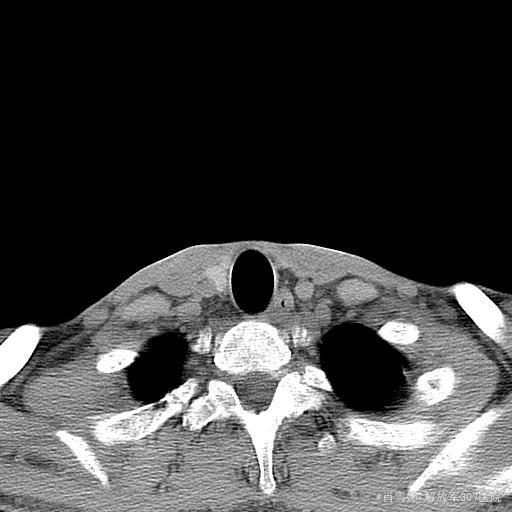

查体:神志清楚,不能独立行走,消瘦体型,胸廓、腰骶部、颈椎等多处骨骼有明显压痛。心肺腹未见明显阳性体征。 辅助检查:PTH:86.61(15-65pg/ml);25-D3:5.8(20-32);ALP:264.8(0-130u/l);血P:0.34(0.89-1.6mmol/l);血Ca:2.2(2.09-2.54mmol/l);骨密度:严重骨质疏松;X线:可见病理性骨折。奥曲肽显像:垂体瘤不除外。颈部CT:左侧甲状旁腺不除外结节样改变。